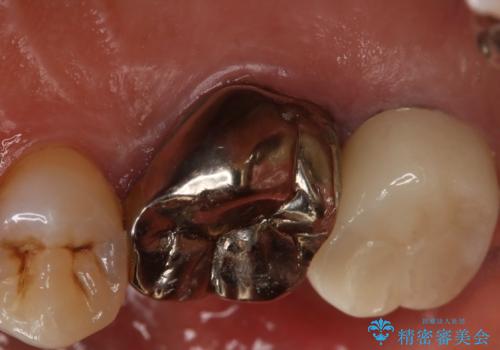

- 右上大臼歯の被せ物が取れたので作り直しを希望された患者様です。

被せ物は白くしたいとのことだったのでフルジルコニアクラウンでの治療を選択しました。

根管治療も必要だったので金属の土台を除去し、新しく土台を立て直した上で被せ物を装着しています。